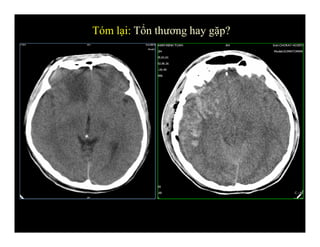

Tóm lại: Tổn thương hay gặp?